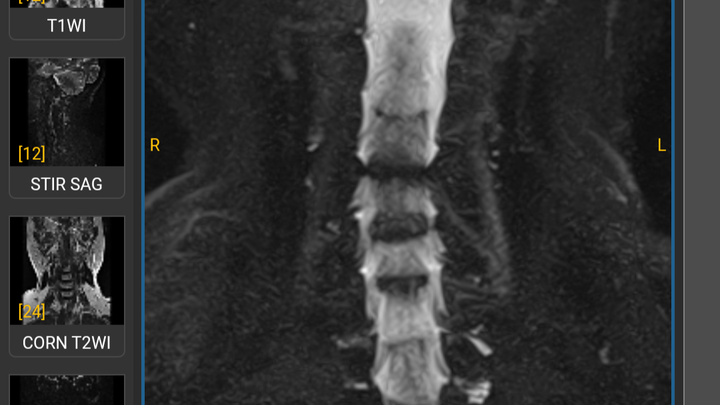

Hola me llamo Soledad de Jesús Tiburcio Cobos tengo 67 años, requiero una cirugía disectomia de columna cervical en las vértebras (C4-C5, C5-C6, C6-C7) y la colocación de cajas auto bloqueantes, de no recibir el tratamiento podría quedar cuadraplejica por lesión en médula, ayúdame a recobrar mi salud para poder seguir siendo independiente. Los fondos recaudados serán utilizados para cubrir los costos de hospitalización, intervención quirúrgica, medicamentos, rehabilitación de la misma.